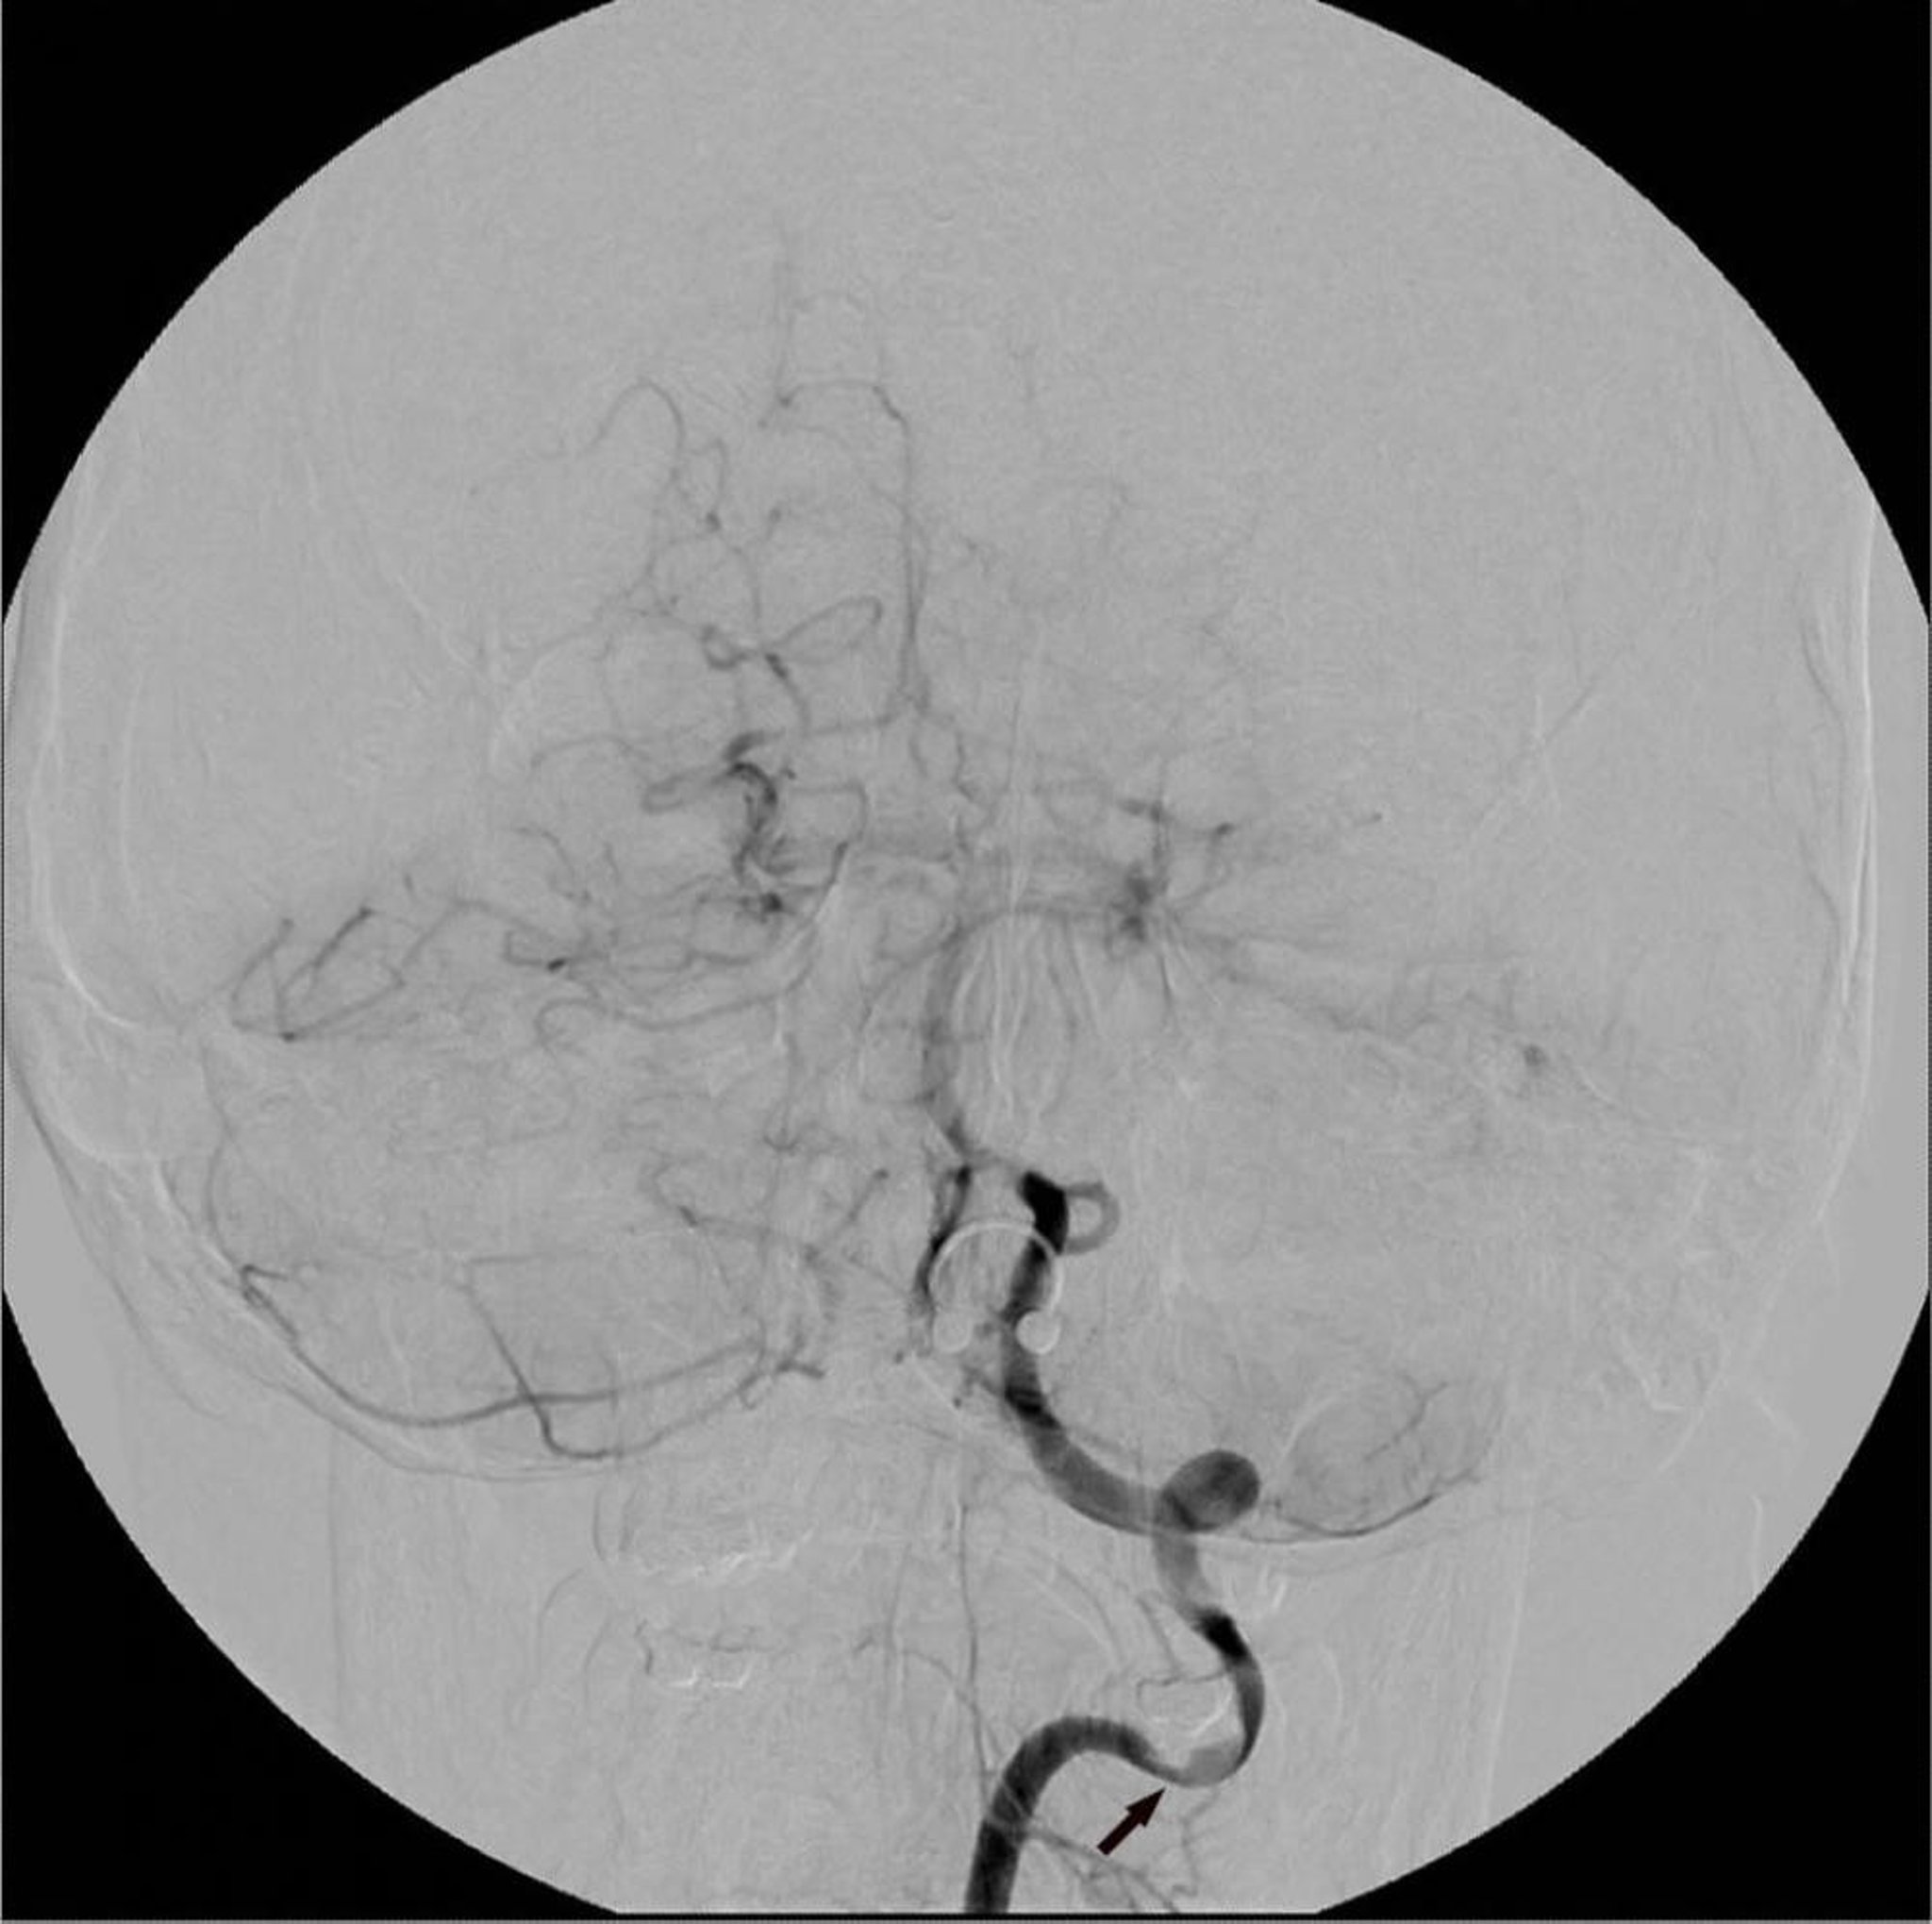

Digital subtraction angiography (DSA) of the left vertebral artery shows a focal area of stenosis (arrow).

Image courtesy of Hakan Ilaslan, MD.